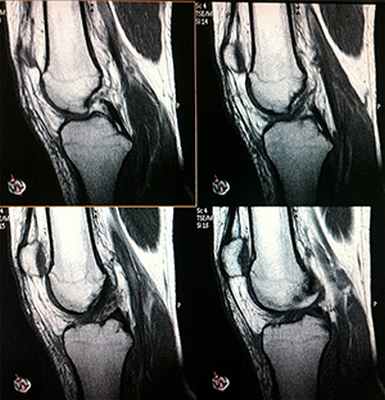

На серии МР-томограмм, взвешенных по Т1, Т2 и протонной плотности с подавлением сигнала от жировой ткани в сагиттальной, аксиальной и корональной плоскостях, визуализируются структуры левого коленного сустава.

Соотношение в коленном и пателло-феморальном суставе правильные.

Суставная щель умеренно сужена, конгруэнтность суставных поверхностей сохранена. Суставной хрящ в медиальных отделах неравномерно истончен, без хондральных дефектов. Межмыщелковые возвышения умеренно заострены. Отмечаются невыраженные краевые костные заострения большеберцовой и бедренной кости, надколенника.

Надколенник (I тип по классификации Wiberg). Хондромаляция 1 степени по системе Outerbridge на уровне латеральной фасетки. Собственная связка надколенника однородного МР-сигнала, ход физиологичный. Поддерживающие связки надколенника прослеживаются, волокна не изменены.

Медиальная и латеральная коллатеральные связки без грубых изменений.

МР-сигнал от передней крестообразной связки неоднородный, ход волокон прослеживается, волокна умеренно разволокнены. Ход задней крестообразной связки прослеживается на всем протяжении, МР-сигнал однородный.

В области заднего рога и тела медиального мениска отмечается горизонтальный разрыв (Stoller IIIa). Латеральный мениск с умеренными дегенеративными изменениями (до Stoller II).

В полости сустава и в супрапателлярной сумке выявляется небольшое количество жидкости. Суставная капсула не утолщена.

В медиальных отделах подвколенной ямки отмечается локальное скопление однородной жидкости, размером 14х9х6 мм.

ЗАКЛЮЧЕНИЕ: МР-признаки горизонтального разрыва заднего рога и тела медиального мениска, дегенеративных изменений левого коленного сустава, передней крестообразной связки. Киста Бейкера. Незначительный синовит, супрапателлярный бурсит.

Рекомендовано: консультация травматолога-ортопеда.